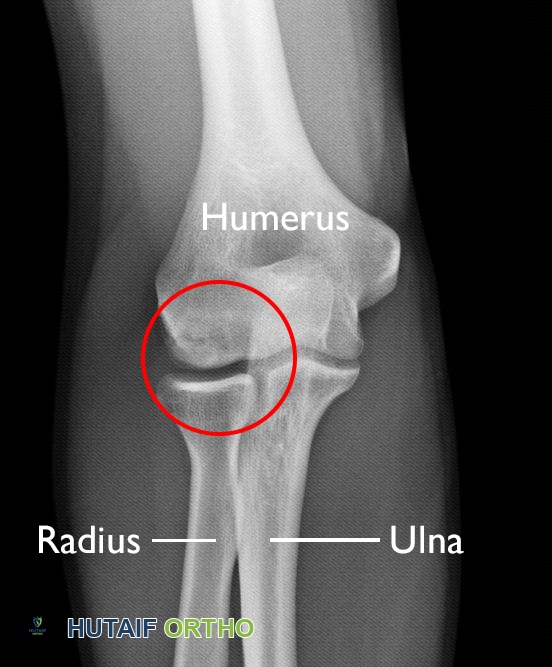

- المرفق (الكوع): يمكن أن تتأثر رؤوس العظام التي تشكل مفصل المرفق، مثل رأس عظم العضد (Humerus) أو رأس عظم الكعبرة (Radius)، مما يؤثر على حركة الذراع والأنشطة اليومية.

تُظهر هذه الأشعة السينية آفة التهاب العظم والغضروف السالخ (المحاطة بدائرة) في عظم العضد (عظم الذراع العلوي) لمراهق.

الصورة مقدمة من ستيوارت ج. فيشر، دكتور في الطب، FAAOS